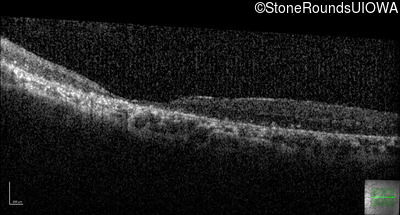

Age at visit: 41 years

This 41 year old man first came to medical attention at age 18 months when exotropia and amblyopia of his right eye were discovered. At age 11 vitreous strands and retinal vascular sheathing were seen. He has had poor night vision and constricted visual fields since his late teens. Later, at age 44 a traction retinal detachment was noted in his left eye and was treated with a scleral buckle.